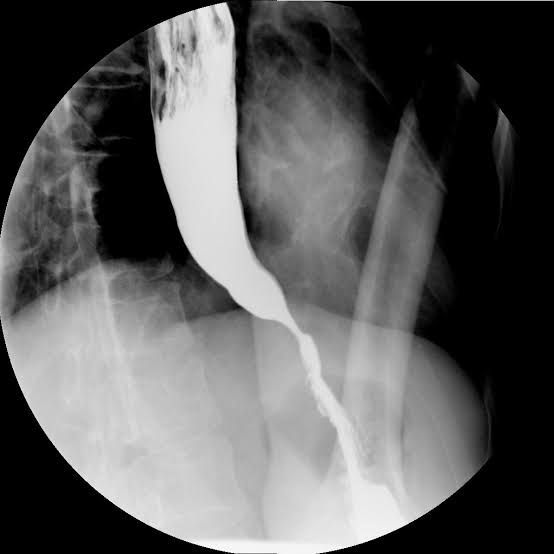

Several treatments are available for achalasia including nonsurgical options (balloon dilation, medications, and botulinum toxin injection) and surgical options. The goal of treatment is to relieve your symptoms by relaxing your lower esophageal sphincter (LES). Your healthcare provider will discuss these options so you both can decide the best treatment for you based on the severity of your condition and your preferences.